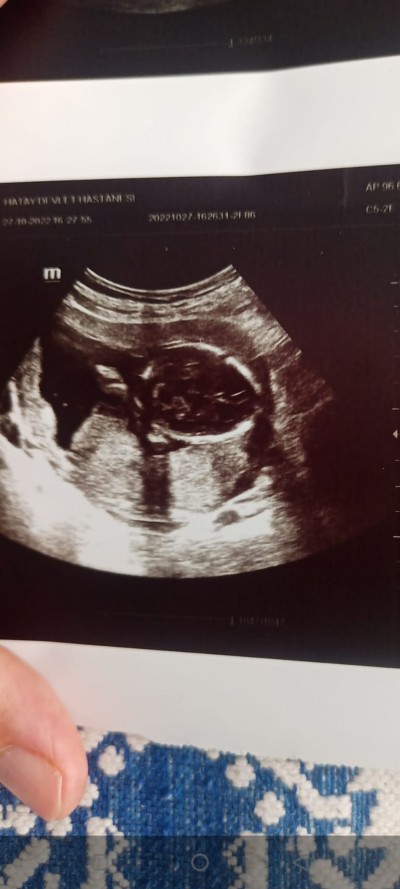

Cinsiyet tahmini yapabilir misiniz kız mı erkek mi

Cinsiyetini bir türlü öğrenemiyorum sizce nedir

Canim bebegin kac haftalik?bide fotdan bebegi ayirt edemedimki

Neresini cekmiski doktor dikkatlr bakiyorum bir turlu cozemedim gecen benimde bi ftraf vardi 100kere baktim anlamadim sonra kuzenim anlamisdi bebegin robot resmini cizib yollamisti ustunden))oyle cozmustum

Cnsyete gelinced 17hafta oldunuz soylemedimi doktor?12+4de soyledi doktorum

Uygun pozisyonu bulamadı bir türlü

Kız bu ne =)) ama içimden erkek geldi. Kac haftaliksin

17 haftalık cnm